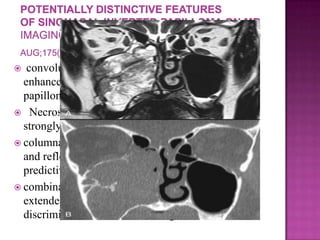

 convoluted cerebriform pattern on T2- or

enhanced T1-weighted images suggests inverted

papilloma as a histologic diagnosis

 Necrosis in a mass with such an appearance

strongly suggests coexistent carcinoma

 columnar pattern is a reliable MRI indicator of IP

and reflects its histological architecture (positive

predictive value of 95.8%)

 combination of this finding with the absence of

extended bone erosion allows for the confident

discrimination of IPs from malignant tumors